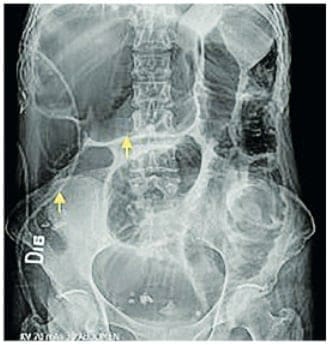

Se realizó una tomografía computarizada (TC) de abdomen con contraste (Figura 2) donde se documentó una zona de transición a nivel del colon sigmoide.

Figura 2. Corte coronal de la tomografía computarizada contrastada de abdomen,

las flechas señalan la estriación del meso del sigmoide.

Fuente: archivo de los autores.